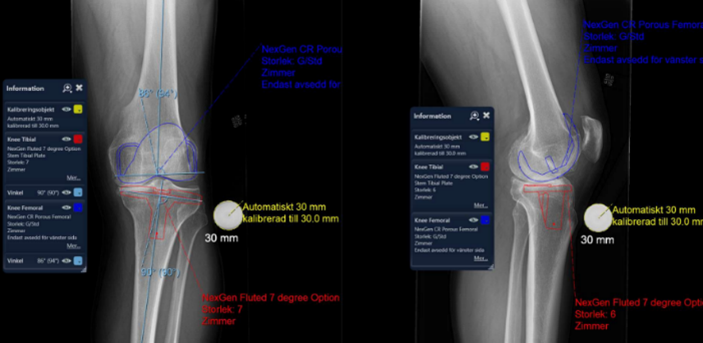

Röntgen inför proteskirurgi knä

• Viktigt i utredning för rätt vinkel av sågning osv. Kulan på bild är 30 mm

• Figursågning för att protesen ska passa perfekt. 6 grader valgus. Tibia rätvinkligt i frontalplan. Vi vill ha o-gradigt i HKA och efter som lårbenshalsen sticker ut lite snett vill vi ha lite valgus.

Så vilka två punkter hjälper ovan oss med vid operation?

A

1. Korrekt benresektion enligt mallning/anatomi

2. Ligamentbalansering: dela strama strukturer så att ligamentbalansen blir korrekt både i flektion och i extension